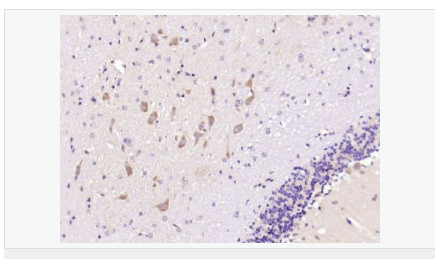

| 產(chǎn)品應(yīng)用 | ELISA=1:5000-10000 IHC-P=1:100-500 IHC-F=1:100-500 IF=1:200-800 (石蠟切片需做抗原修復(fù)) not yet tested in other applications. optimal dilutions/concentrations should be determined by the end user. |

| 產(chǎn)品介紹 | This gene encodes a member of the corticotropin-releasing factor family. The encoded preproprotein is proteolytically processed to generate the mature neuropeptide hormone. In response to stress, this hormone is secreted by the paraventricular nucleus (PVN) of the hypothalamus, binds to corticotropin releasing hormone receptors and stimulates the release of adrenocorticotropic hormone from the pituitary gland. Marked reduction in this protein has been observed in association with Alzheimer's disease. Autosomal recessive hypothalamic corticotropin deficiency has multiple and potentially fatal metabolic consequences including hypoglycemia and hepatitis. In addition to production in the hypothalamus, this protein is also synthesized in peripheral tissues, such as T lymphocytes, and is highly expressed in the placenta. In the placenta it is a marker that determines the length of gestation and the timing of parturition and delivery. A rapid increase in circulating levels of the hormone occurs at the onset of parturition, suggesting that, in addition to its metabolic functions, this protein may act as a trigger for parturition. [provided by RefSeq, Nov 2015] Function: This hormone from hypothalamus regulates the release of corticotropin from pituitary gland. Subunit: Interacts (via C-terminus) with CRFR1 (via N-terminal extracellular domain). Subcellular Location: Secreted. Similarity: Belongs to the sauvagine/corticotropin-releasing factor/urotensin I family. SWISS: P06850 Gene ID: 1392 Database links: Entrez Gene: 1392 Human Entrez Gene: 12918 Mouse Omim: 122560 Human SwissProt: P06850 Human SwissProt: Q8CIT0 Mouse Unigene: 75294 Human Unigene: 290689 Mouse Unigene: 10349 Rat Important Note: This product as supplied is intended for research use only, not for use in human, therapeutic or diagnostic applications. CRF陽性神經(jīng)元的胞體廣泛分布于下丘腦的室旁核、背縫核和藍(lán)斑核,這些區(qū)域也是去甲腎上腺素(NE)神經(jīng)元與5-羥色胺(5-HT)神經(jīng)元密集的區(qū)域。 CRF既具有神經(jīng)遞質(zhì)的性質(zhì)又具有神經(jīng)激素的性質(zhì)。CRF是聯(lián)系神經(jīng)系統(tǒng)與內(nèi)分泌系統(tǒng)的橋梁,在情感障礙疾患如焦慮和抑郁的發(fā)病中發(fā)揮重要作用. |